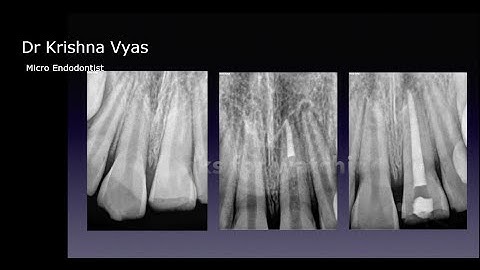

Management of Open apex using MTA barrier #shorts#mta #openapex